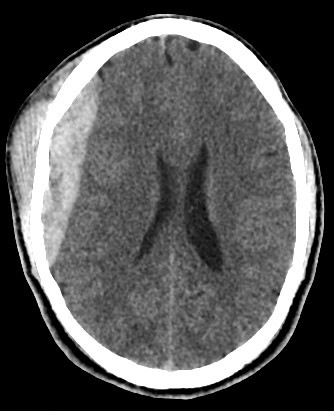

• Biconvex (lentiform) hyperdense collection adjacent to the inner table of the skull.

• Does not cross sutures (limited by dural attachments).

• Underlying skull fracture commonly visible, especially in the temporal region.

• Mass effect: midline shift, compression of adjacent sulci or ventricles.

• Lentiform extra-axial collection with dural attachment but no extension across sutures.